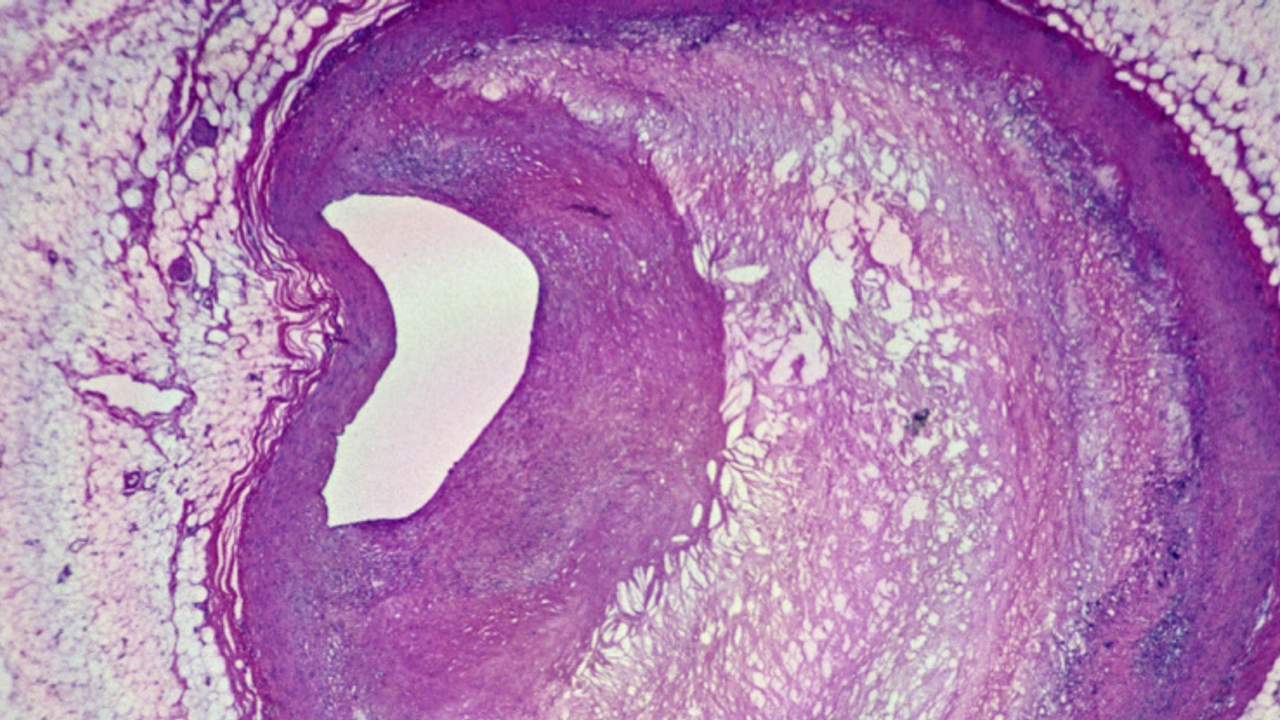

Üç yıla yakın takip edilen hastalar arasında, damarlarında mikroplastik bulunanların felç, kalp krizi ya da ölüm riskinin 4,5 kat daha yüksek olduğu belirlendi. Mikroskop altında yapılan incelemelerde, bağışıklık hücrelerinin içinde ve yağlı plaklarda pürüzlü plastik parçaları da gözlemlendi.